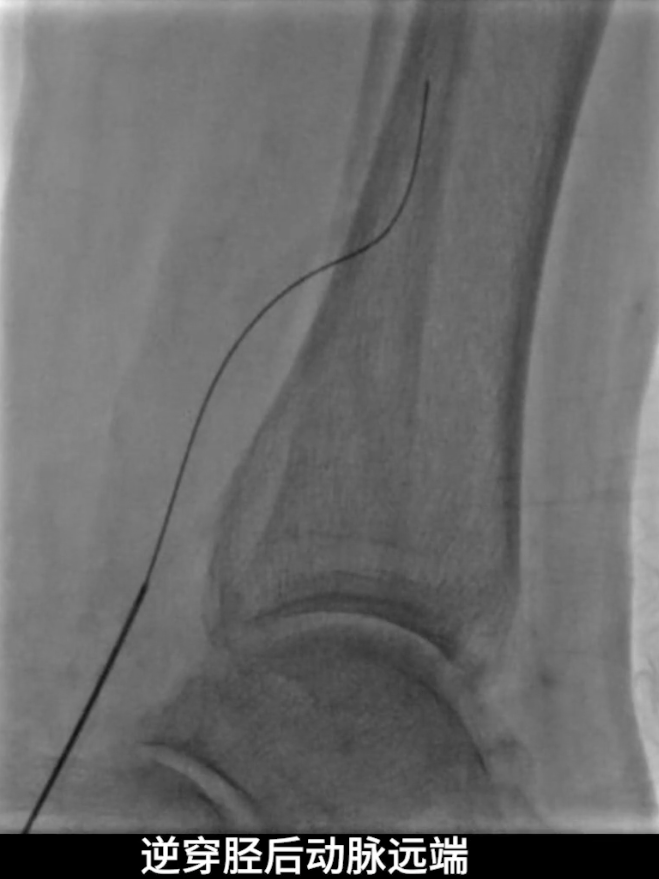

逆穿技术应用:改为逆穿胫后动脉远端,支撑导管配合V18导丝经交通支逆行进入腓动脉远端,逐步推送导丝导管通过胫腓干闭塞段,直至腘动脉近端真腔,与近端导管完成对接,建立膝下流出道操作轨道。